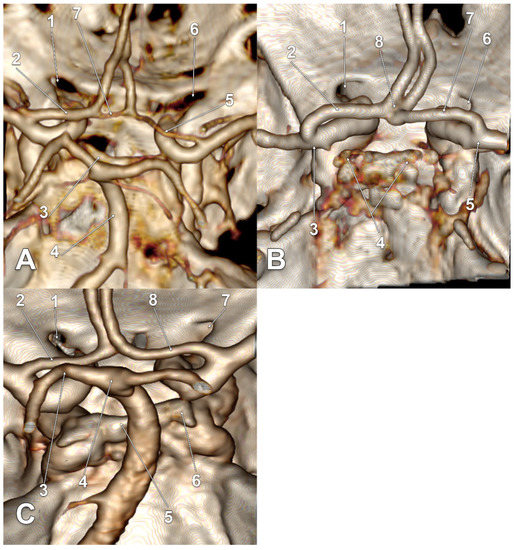

| Gender | Right Side | Left Side | Other Variations | Figure |

|---|---|---|---|---|

| M | type 3 IO A1 SCar | type 3 IO A1 SCar | high BA bifurcation | Figure 3A |

| M | type 3 IO A1 | type 3 IO A1 | Figure 2D | |

| M | type 2 IO A1 | type 1 IO A1 SCar | fenestrated AComA, hypoplastic left A1 | Figure 2A |

| M | type 2 IO A1 | type 2 IO A1 SCar | Figure 4C | |

| M | type 2 IO A1 | type 2 IO A1 | Figure 4A | |

| M | type 2 IO A1 | type 2 IO A1 | – | |

| M | type 2 IO A1 | type 2 IO A1 | Figure 5B | |

| F | type 2 IO A1 | type 2 IO A1 | rotated BA, left PCA displaced towards the ipsilateral A1 ACA | Figure 4D |

| F | type 2 IO A1 | type 2 IO A1 | duplicated AComA | Figure 4B |

| F | type 2 IO A1 SCar SClin | type 1 IO A1 | supraclinoid right A1 | Figure 2C |

| F | type 2 IO A1 | type 2 IO A1 | Figure 3D | |

| F | type 2 IO A1 | type 2 IO A1 | Figure 3B,C | |

| F | type 2 IO A1 | type 2 IO A1 | hypoplastic right A1 | |

| F | type 2 IO A1 SCar | type 2 IO A1 SCar | rotated AComA, hypoplastic right A1 | Figure 5A |

| F | type 2 IO A1 | type 2 IO A1 | rotated BA, left PCA displaced towards the ipsilateral A1 ACA | Figure 5C |

| F | type 1 IO A1 | type 2 IO A1 | left bihemispheric ACA | Figure 2B |